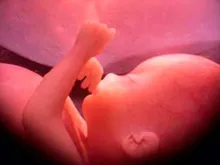

Investigadores afirmam que às 17 semanas feto já experimenta sentimentos

Um grupo de investigadores na Grã-Bretanha demonstrou com uma exploração 4-D, que um feto de 17 semanas de gestação pode... Leia mais